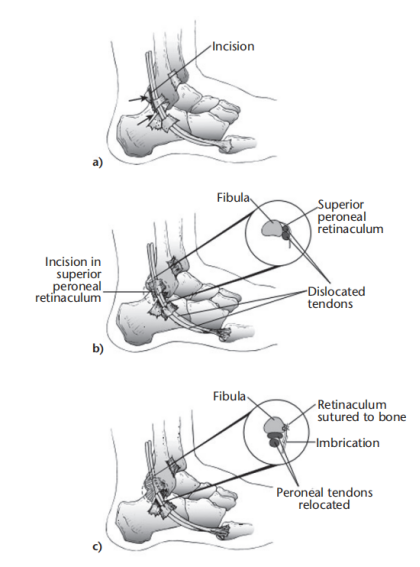

(3)手术方法可分为以下5类:

如不合并其他病理改变,可将支持带和骨膜直接缝合于外踝骨质上。

SPR撕脱开放手术锚钉修复

SPR撕脱关节镜手术锚钉修复

使用跟腱、跖肌腱、腓骨短肌腱等肌腱的一部分加强固定腓骨支持带。

通过切除腓骨后方部分骨质,可以加深腓骨沟,改变、并增加了腓骨肌腱的稳定。

内镜下腓骨沟加深手术

大部分急性损伤可以使用直接缝合修复,对慢性损伤则需根据患者的具体病理改变选择,如单纯的支持带结构损伤,可以直接缝合修复。如果直接修复不够稳定,需用其他组织加强。如果腓骨外踝窝较浅时,就需要使用加深手术。